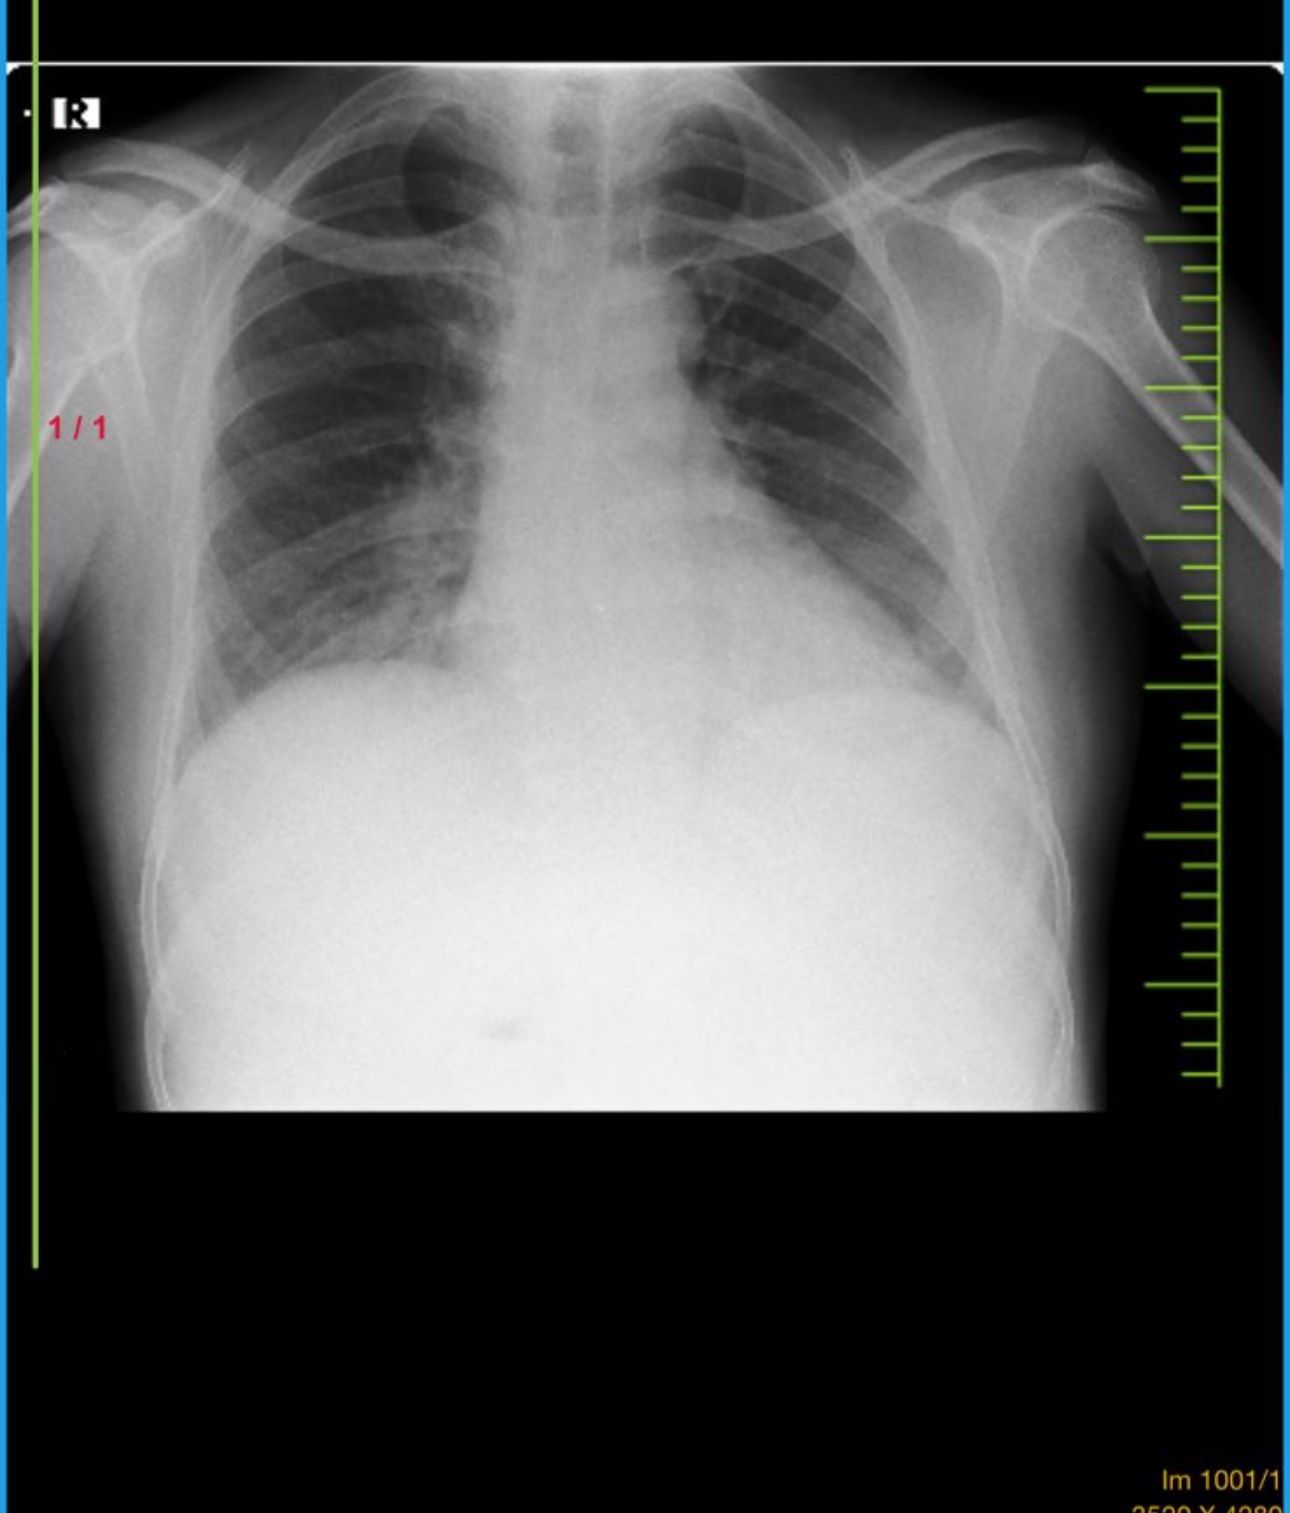

RS:B/L AE present,nvbs

CVS S1S2 + CNS NFND RS BAE + P/A SOFT,NT